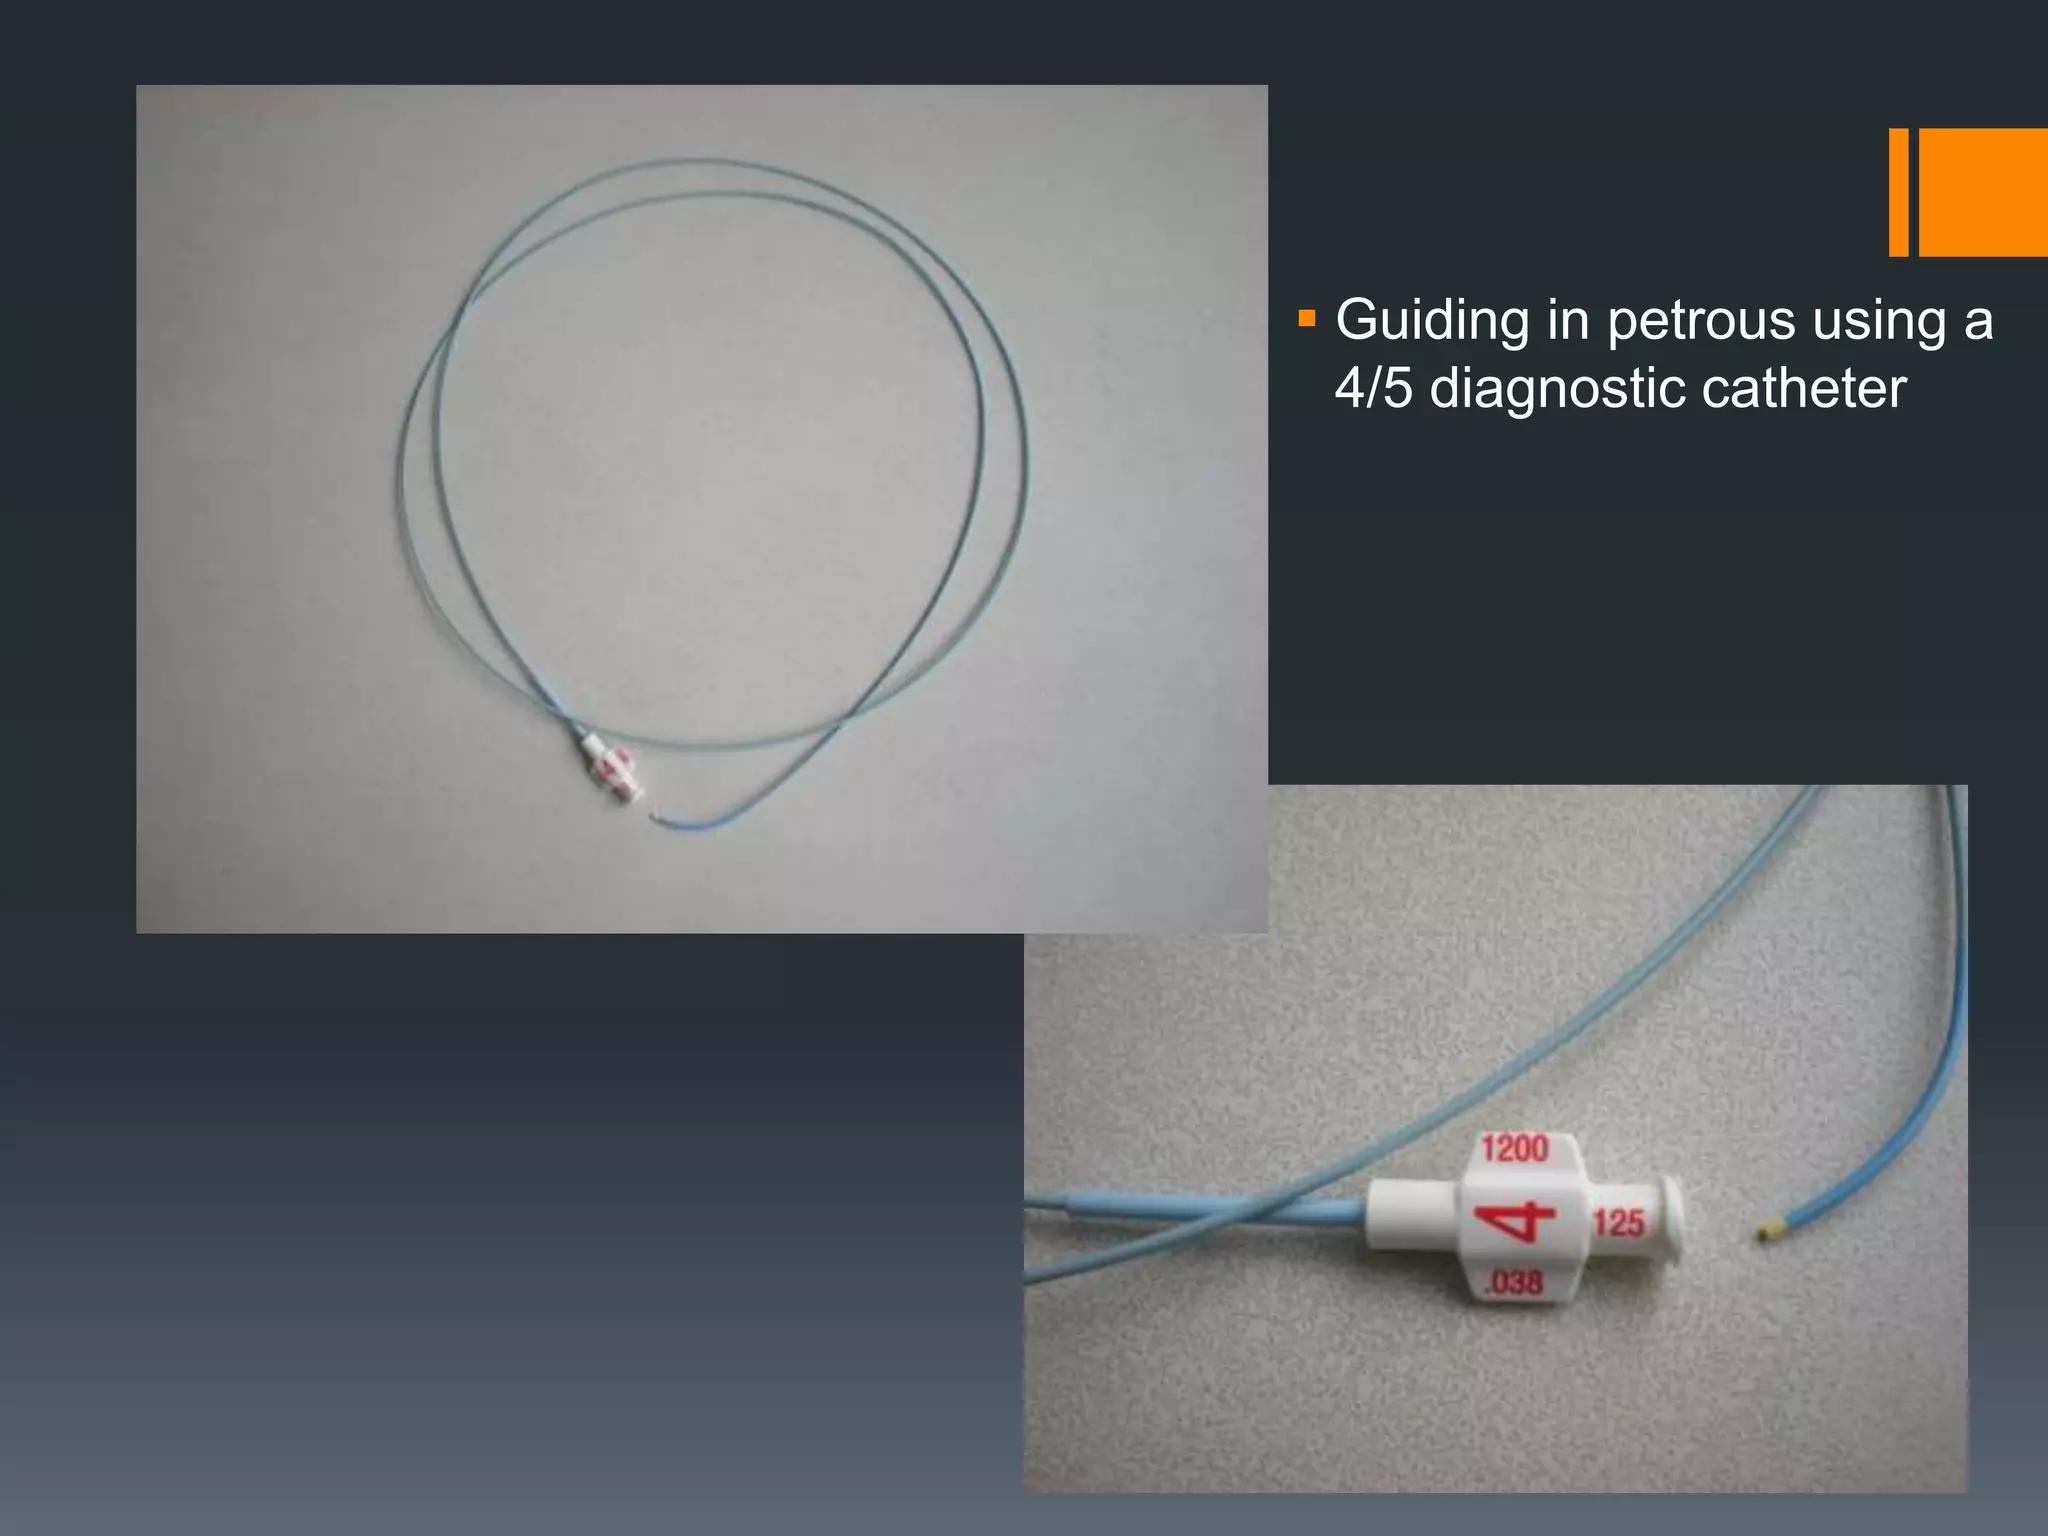

This document discusses tricks and techniques for difficult cannulations during neurointerventional procedures. It outlines strategies for accessing the aortic arch, internal carotid artery (ICA), and areas distal to aneurysms. Long sheaths, distal access catheters, and co-axial techniques are presented as options that have improved cannulation success. Guidance on sheath and catheter selection is provided for different vessel paths. The importance of catheter placement as high as possible in the ICA is emphasized. Reverse curve cannulations are also mentioned. Overall, the document stresses that careful cannulation is critical for procedural success and different strategies may be needed depending on the vessel target.